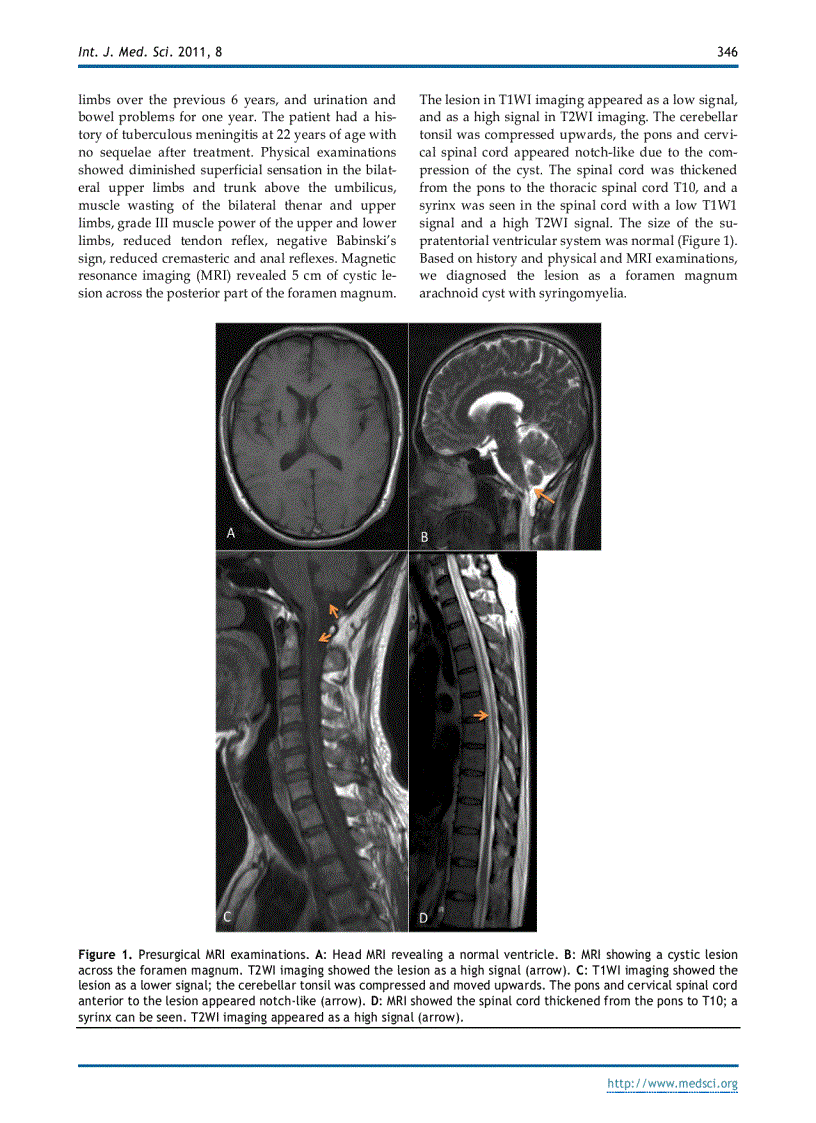

image for page Báo cáo y học Foramen Magnum Arachnoid Cyst Induces Compression of the Spinal Cord and Syringomyelia Case Report and Literature Review